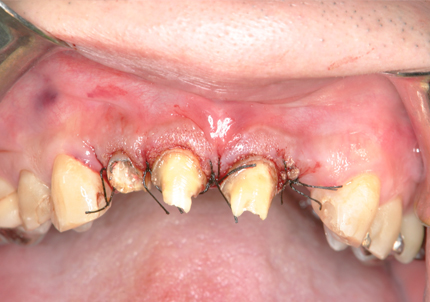

3.歯冠長延長術(2014年11月)

➡ 歯冠長延長術とは・・・歯ぐきや骨の位置を調整して、歯の見えている部分(歯冠)を意図的に長くする治療。歯ぐきがかぶって歯が短く見える審美的な問題、歯周病治療や補綴治療を成功させるための前処置等として行われる。

【 縫合 】

【 歯周パック 】

4.抜歯・術後経過

歯冠長延長術、矯正的抜歯により

前歯部歯頚線が揃う(2014年12月)